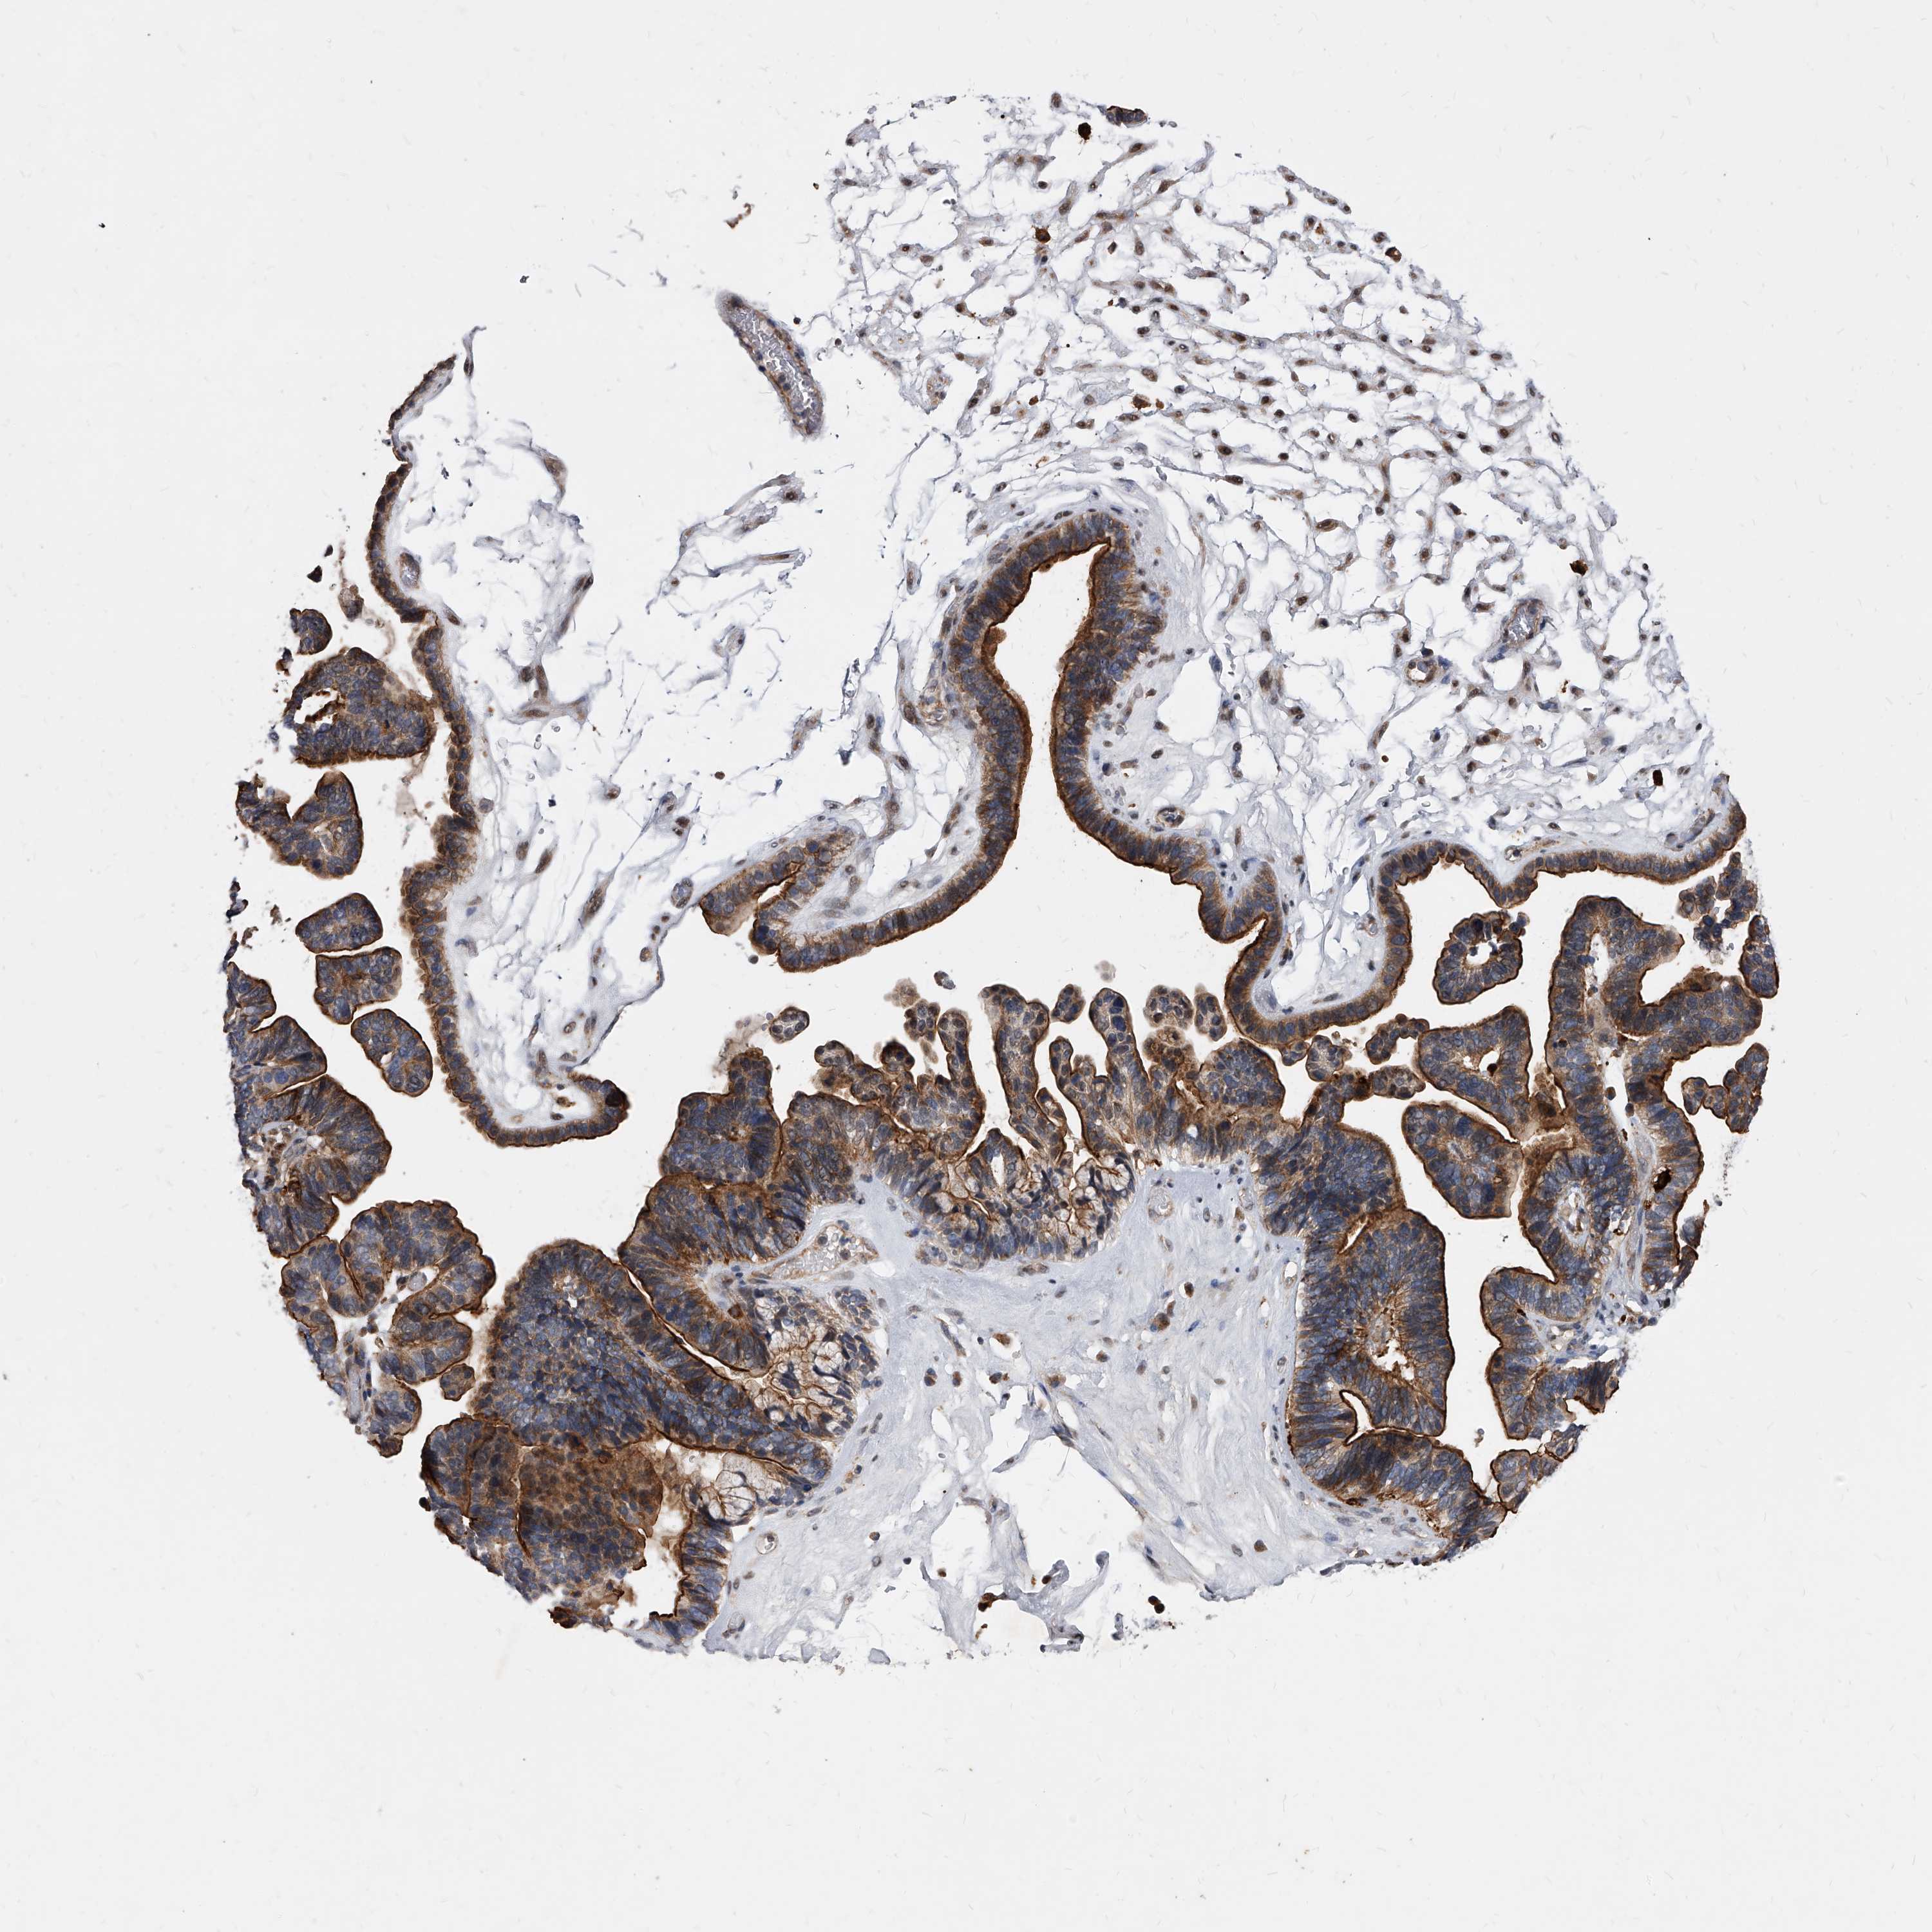

OVARIAN CANCER - Protein expressioni

A mouse-over function shows sample information and annotation data. Click on an image to view it in a full screen mode. Samples can be filtered based on level of antibody staining by selecting one or several of the following categories: high, medium, low and not detected. The assay and annotation is described here.

Note that samples used for immunohistochemistry by the Human Protein Atlas do not correspond to samples in the TCGA dataset.

Antibody stainingi

Antibody staining in the annotated cell types in the current human tissue is reported as not detected, low, medium, or high, based on conventional immunohistochemistry profiling in selected tissues. This score is based on the combination of the staining intensity and fraction of stained cells.

Each image is clickable and will lead to virtual microscopy that enables deeper exploration of all samples and also displays staining intensity scores, fraction scores and subcellular localization as well as patient and tissue information for each sample.

Antibody HPA029242

Staining

High

Medium

Low

Not detected

Intensity

Strong

Moderate

Weak

Negative

Quantity

>75%

75%-25%

<25%

None

Location

Nuclear

Cytoplasmic/membranous

Cytoplasmic/membranous,nuclear

Cystadenocarcinoma, serous, NOS

Carcinoma, endometroid

Cystadenocarcinoma, mucinous, NOS

Carcinoma, NOS